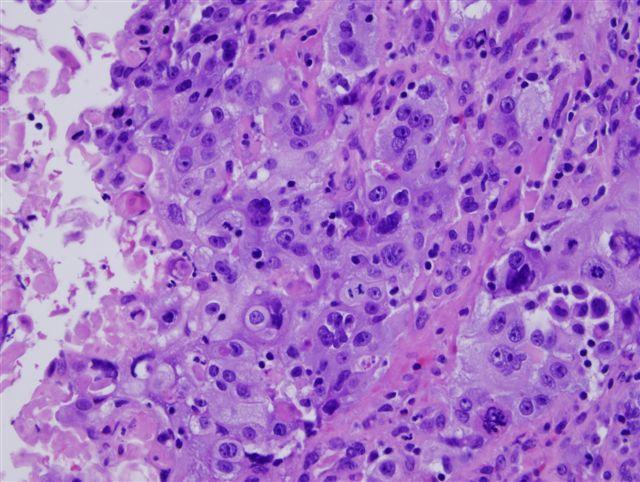

Как выглядят раковые клетки при проведении цитологии шейки матки

Раковые клетки отличаются от нормальных по нескольким признакам:

• Полиморфизм. В мазке можно увидеть клетки одной ткани, но с различными размерами, формами и структурой.

• Анизоцитоз. Наблюдается изменение размера клеток — как уменьшение, так и увеличение.

• Анизокариоз. Ядра клеток могут быть как увеличенными, так и уменьшенными. Ядро — центральный элемент клетки, содержащий генетический материал и необходимый для деления.

• Изменение формы и количества ядер. Ядра раковых клеток могут быть неправильной формы, бесформенными и с неровными контурами. Встречаются двухъядерные и многоядерные клетки, а иногда можно увидеть только ядра без других клеточных элементов.

• Изменения в цитоплазме. При окрашивании цитоплазма имеет неравномерную окраску.

Цитологическое исследование

Раковые опухоли характеризуются усиленным ростом, поэтому в образце, взятом для цитологии шейки матки, обнаруживаются делящиеся клетки. Часто деление происходит с нарушениями, что называется атипичным митозом.

Чем менее зрелые клеточные структуры находятся в мазке, тем ниже дифференцировка опухоли. Этот показатель обозначается буквой G, а рядом стоит цифра, указывающая на степень дифференцировки. Чем выше цифра, тем злокачественнее рак.